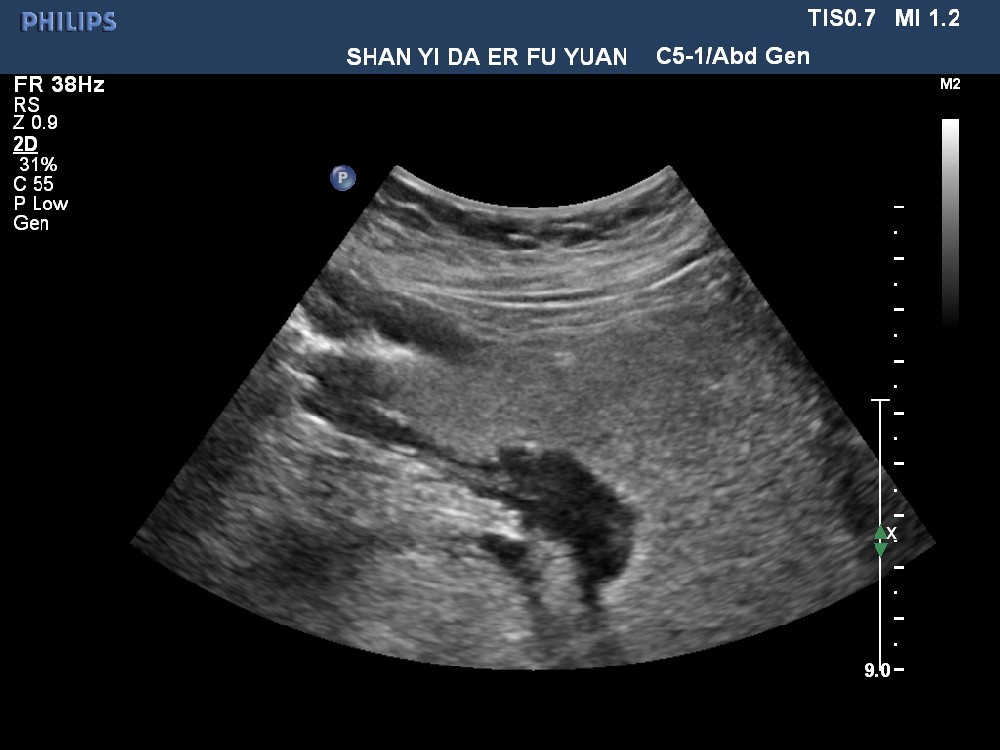

胃癌